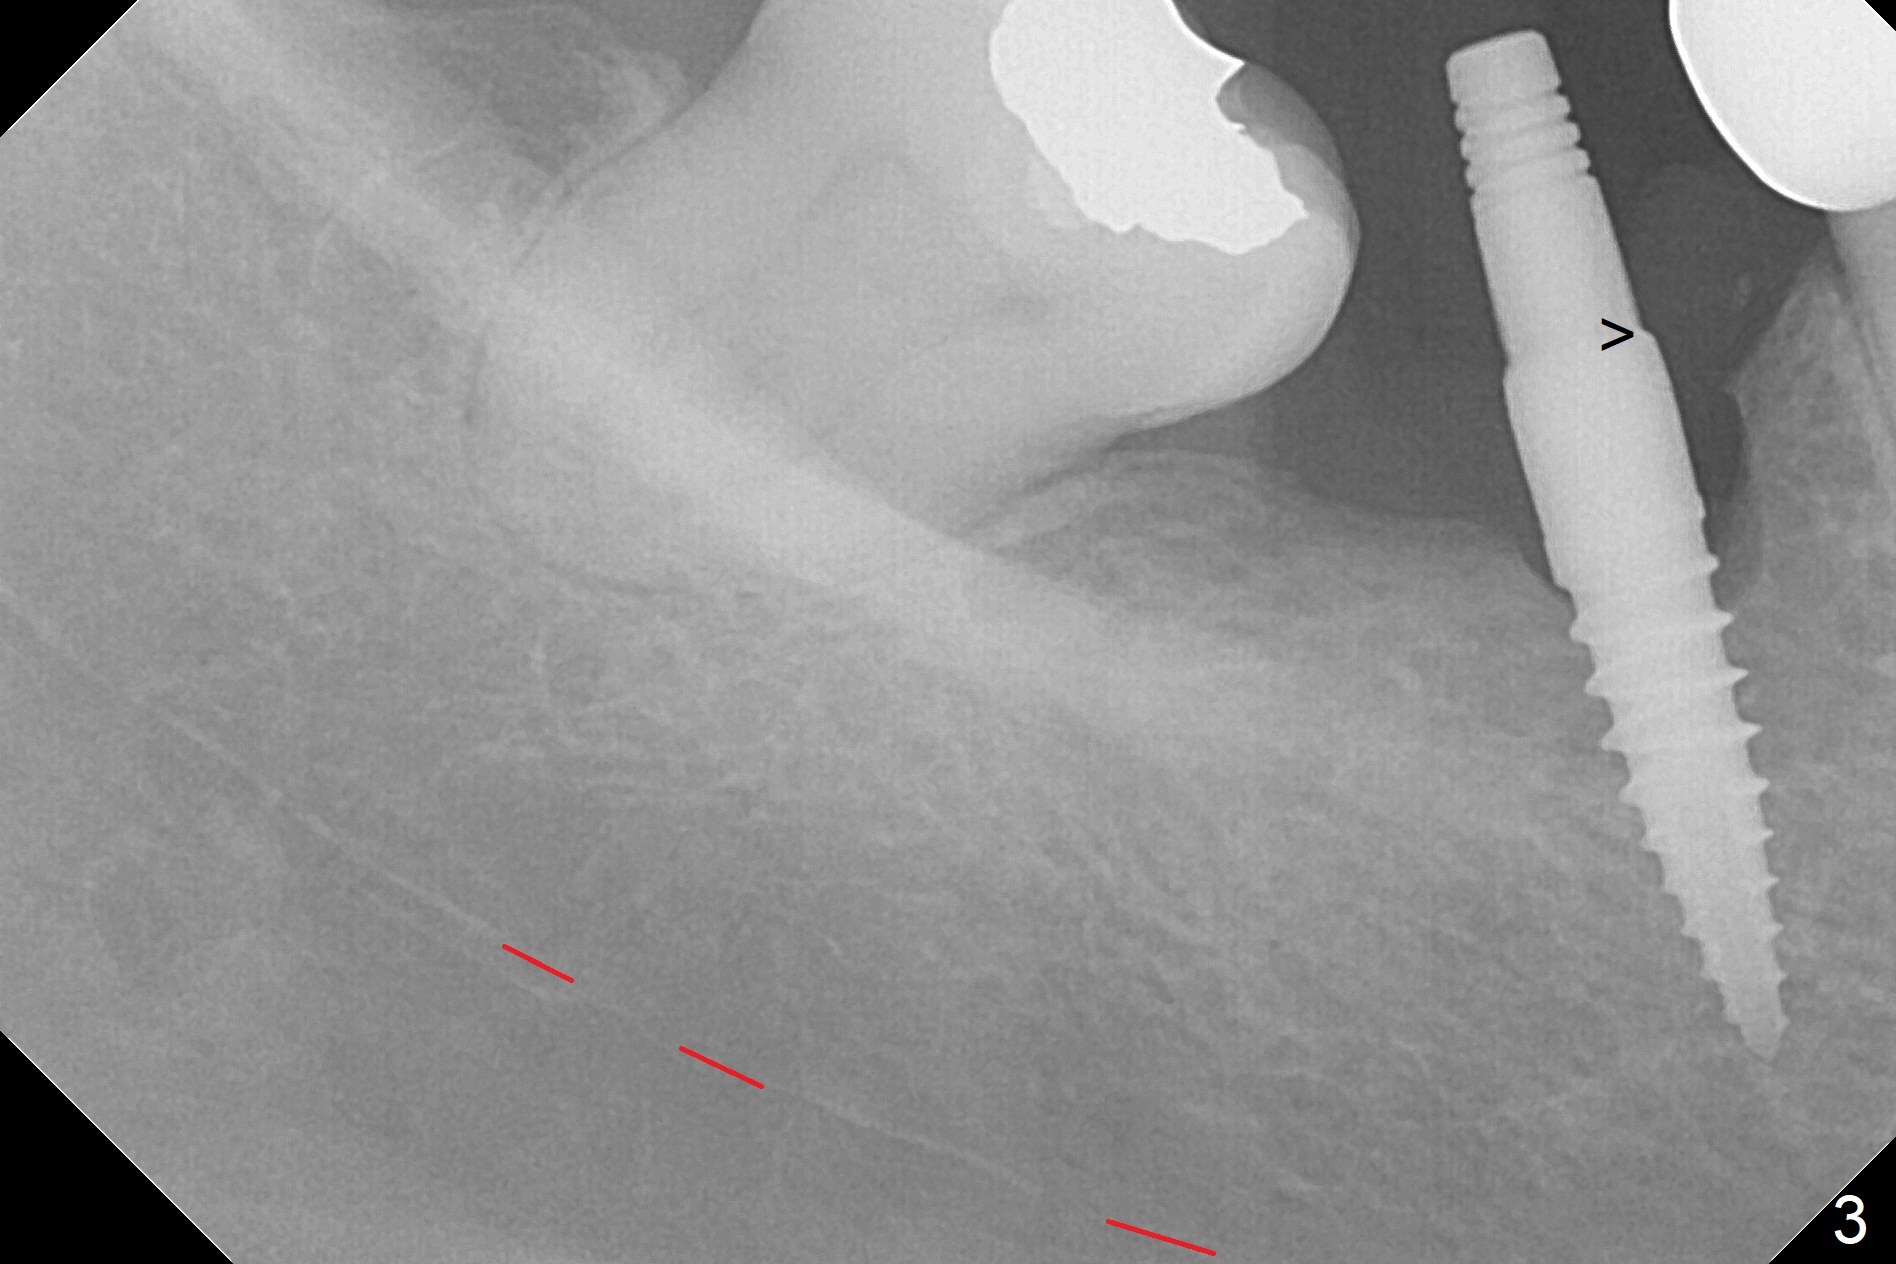

Incision reveals a narrow ridge and a narrow mesiodistal space at #30 (Fig.1). It seems that a 1-piece implant is indicated. Due to limited mouth opening, a 1.2 mm drill is unstable in place after use for 10 mm; instead a 1.5 mm drill is able to be inserted for 8 mm (Fig.2). A 3x10(2) mm 1-piece dummy implant is placed with 40 Ncm at an apparently acceptable level (Fig.3 >). Clinically a few threads are exposed buccally. When a definitive implant with the same dimension is inserted with 45 Ncm, it looks seated too deep (Fig.4,5). The latter is noted after suturing. The implant is backed up for a few turns so that the length of the abutment appears a little more reasonable. Introspectively, a 4 mm cuff should have been used after ridge reduction. Although there is no bone loss 4 months postop (Fig.6), the abutment margin (Fig.7 arrow) is subgingival (red dashed line: gingival margin). Diode laser is used for gingivectomy prior to impression. The bone density around the implant increases 11 months post cementation (Fig.8 *), probably related to recurrent #18 infection. The patient uses floss after meal.